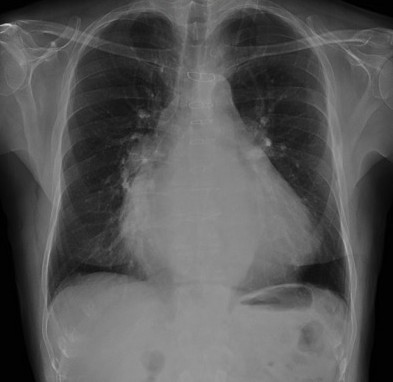

CASO: Postoperado de cirguía cardiovascular.

Hallazgos:

- Cardiomegalia.

- En la placa lateral se observa como el VD sobrepasa la entrada de la vena cava inferior.

- Existe redistribución perihiliar, singos de congestión vascualr por fallo cardiaco.

- Suturas de esternotomía media.

Ratio Arteria / Bronquio:

Normalmente, lo vaos en los lóbulos superior son más pequeños que el bronquio que los acompaña con un ratio de 0.85. A nivel de los hilios, son iguales y en los lóbulos superiores son más grandes con un ratio de 1.35.

Cuando hay redistribución de la sangre pulmonar, habrá un ratio aumentado entre la arteria y el bronquio en los lóbulos superiores y medios. Esto se ve mejor en la región perihiliar.